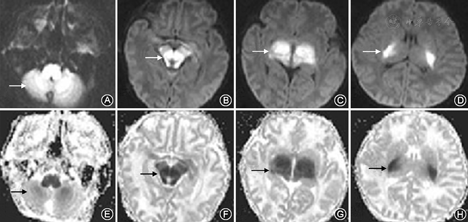

患儿男,8 d,胎龄39周,出生体重3 300 g,因"少吃少动4 d,加重伴阵发性肌张力增高2 d"入院。入院查体:T 36.4 ℃,P 130次/min,R 40次/min,BP 80/50 mmHg,体重3 100 g;神志清,反应差,呼吸平稳,前囟平软,颈软,无抵抗,心肺听诊(-),肝脾肋下未及,腹壁皮肤弹性稍差,四肢肌张力尚可,拥抱、觅食反射弱,其余原始反射未引出。入院6 h后出现频繁抽搐,同时伴有双手划船样动作,肌张力持续增高,张口受限,拒食。查血常规及C反应蛋白正常,血气分析示代谢性酸中毒、血氨升高。头颅CT检查示双侧脑白质密度减低,脑脊液常规正常、培养阴性。予以抗惊厥及对症处理后病情仍逐渐加重,入院第2天出现叹气样呼吸,血气分析示代谢性酸中毒合并呼吸性酸中毒,予以同步间歇指令通气。结合临床表现,考虑遗传代谢病可能,立即行血、尿遗传代谢筛查及头颅MRI检查。入院第3天头颅MRI弥散加权成像序列(DWI)提示两侧小脑齿状核、脑干、丘脑、内囊后肢对称性高信号,表观扩散系数(ADC)呈低信号改变,提示MSUD高度可疑,见图1。血液串联质谱检查结果:亮氨酸3 411.81 μmol/L,缬氨酸600.20 μmol/L,均明显增高。立即予以禁食,维生素B1肌肉注射,鼻饲MSUD特殊奶粉。1周后院外尿液气相色谱-质谱检查结果:乳酸、2-羟基异戊酸、2-羟基异己酸、4-羟基苯乳酸、亮氨酸、缬氨酸显著升高,确诊MSUD。患儿需持续机械通气,家属放弃治疗自动出院。出院第2天死亡。

临床上未经筛查的新生儿MSUD极易误诊为败血症、神经系统疾病及其他导致惊厥的疾病,如缺氧缺血性脑损伤、低血糖、破伤风等[38]。本组40例中仅11例就诊早期考虑遗传代谢病或MSUD,其他病例多有误诊。排在前3位的误诊疾病分别为败血症、中枢神经系统感染或脑病和新生儿肺炎,需引起重视。MSUD确诊主要依据血串联质谱或尿气相色谱/质谱分析,对于可疑患儿应尽早留取标本送检。头颅MRI可用于MSUD的诊断[39]。于文婷和毛健[23]报道,在血或尿液氨基酸分析报告回报之前行头颅MRI及频谱检查有助于早期诊断,并可作为疾病预后的有效评价手段用于临床随访研究。MSUD的头颅MRI成像特征为弥漫性脑白质水肿,侧脑室旁、基底节区、脑干、小脑部位T2WI及DWI高信号影,在T1WI及ADC表现为低信号影,以基底节与脑干为著[40]。本例患儿随病情进展高度怀疑MSUD后及时取血、尿标本,发现血、尿支链氨基酸均显著升高。患儿入院后第3天头颅MRI提示DWI序列两侧小脑齿状核、脑干、丘脑、内囊后肢对称性高信号,ADC呈低信号改变,提示MSUD高度可疑。结合患儿病史、临床症状、体征及实验室检查结果,新生儿MSUD诊断成立。